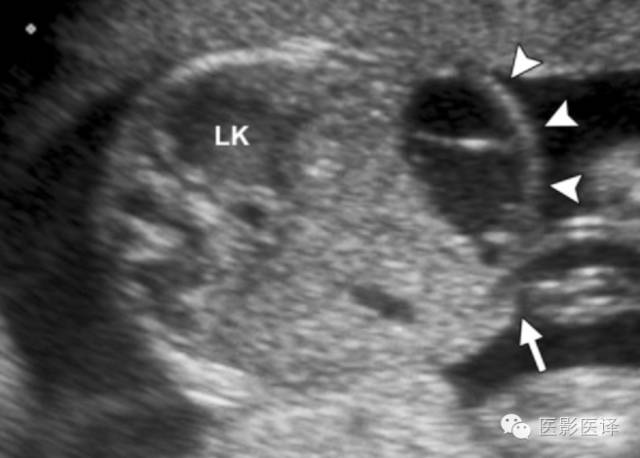

多囊性肾发育不良

MCDK(多囊性肾发育不良)是一种非遗传性肾发育不良。MCDK的超声表现包括多发的肉眼可见的、不相通的无回声囊肿替代肾组织,并严重地扭曲肾脏外形(图9)。一个多囊性肿块可依据它位于靠近脊柱肾窝的位置来确定其肾脏起源。肾盂和肾盏无法辨别,几乎总能观察到肾盂输尿管交界处闭锁。大多数MCDK病历是单侧的(80%),受累肾脏无功能。MCDK通常随着时间的推移渐退化;在9个月到10年完全退化率为19%-74%。肾脏初始长度6.2厘米或更少可以很好地预测受累肾脏完全退化。